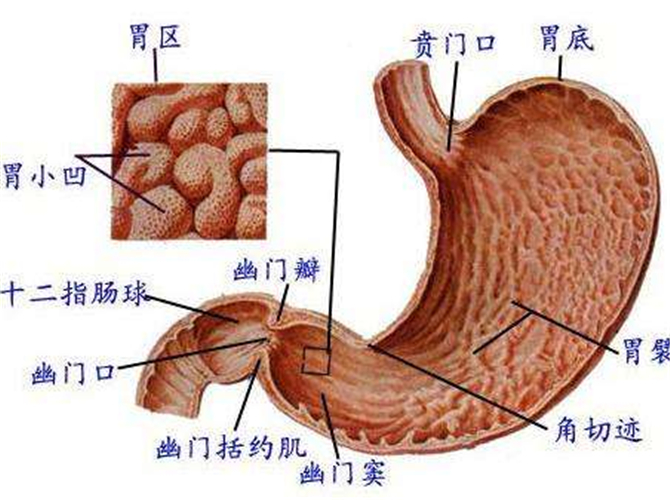

急性胃炎

急性胃炎胃部